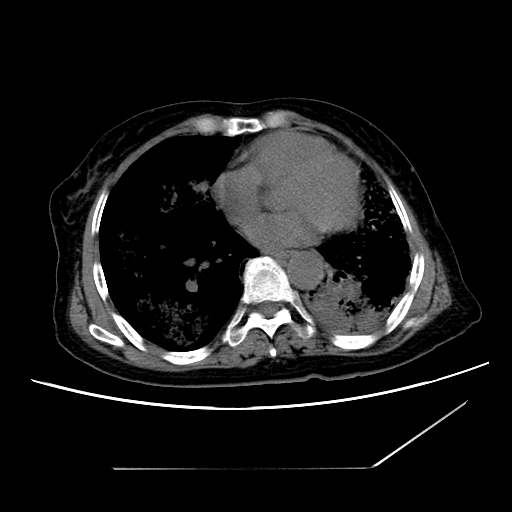

1、左肺中央型肺癌并双肺弥漫性转移   2、双肺部感染    3、肺大泡     4、左侧胸腔积液

双侧肺弥漫性病变,可见“空泡征”及“蜂窝征”,考虑肺泡癌可能性大,左侧胸腔积液,考虑胸膜受累可能!

1)不排除肺泡癌可能。2)左侧胸腔积液。